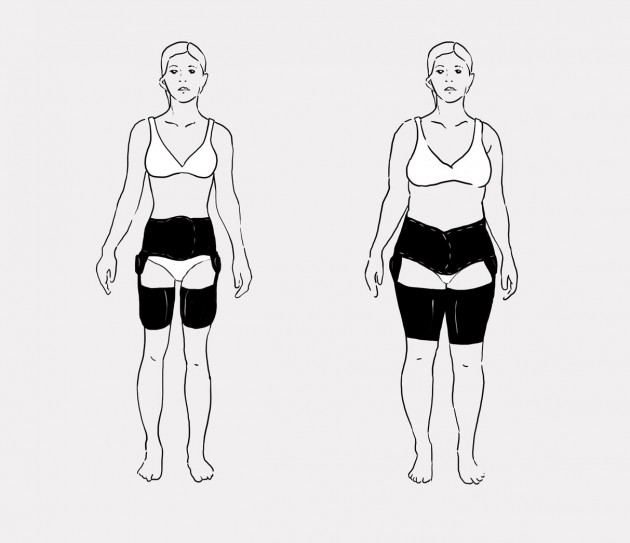

Tabela rozmiarów

| Rozmiar | Obwód w pasie | Sposób dokonywania pomiaru |

|---|---|---|

| Uniwersalny | min 75 – max 125 cm |  |

Maksymalna waga użytkownika do 75kg.

Całkowita długość ortezy:

min: 53 cm

max: 67 cm

Orteza VIPERdual to orteza stabilizująca stawy biodrowe, pozwalająca na regulację ich ruchomości w zakresie co 15 stopni bądź na całkowite ich unieruchomienie. Orteza została wykonana z surowca ActiveDistance oraz ActiveDistance II i wyposażona w uniwersalny kosz biodrowy, dwie opaski udowe oraz dwie jednoosiowe szyny boczne z regulacją ich długości oraz kąta zgięcia i wyprostu co 15 stopni.

Kosz biodrowy posiada anatomiczną konstrukcję pozwalającą na płynną regulację jego obwodu. Regulacja ta jest możliwa dzięki funkcji samoszczepnej surowca, z którego wykonano wyrób, oraz dzięki tylnemu zapięciu. Obwód kosza dopasowuje się do danego pacjenta, poprzez odcięcie zbędnej części ortezy, wzdłuż specjalnie przygotowanych kanałów. Przednie zapięcie kosza biodrowego, zostało tak zaprojektowane, aby pasowało do każdego typu sylwetki.

Dodatkowo, kosz biodrowy wyposażono w dwie plastikowe peloty boczne, w które zamontowano szyny ortopedyczne oraz dwa komplety mocnych pasów obwodowych z możliwością płynnej regulacji ich długości.

W wyrobie zastosowano również dwie opaski udowe, z których każdą wyposażono w pelotę plastikową i dwa pasy obwodowe o regulowanej długości.